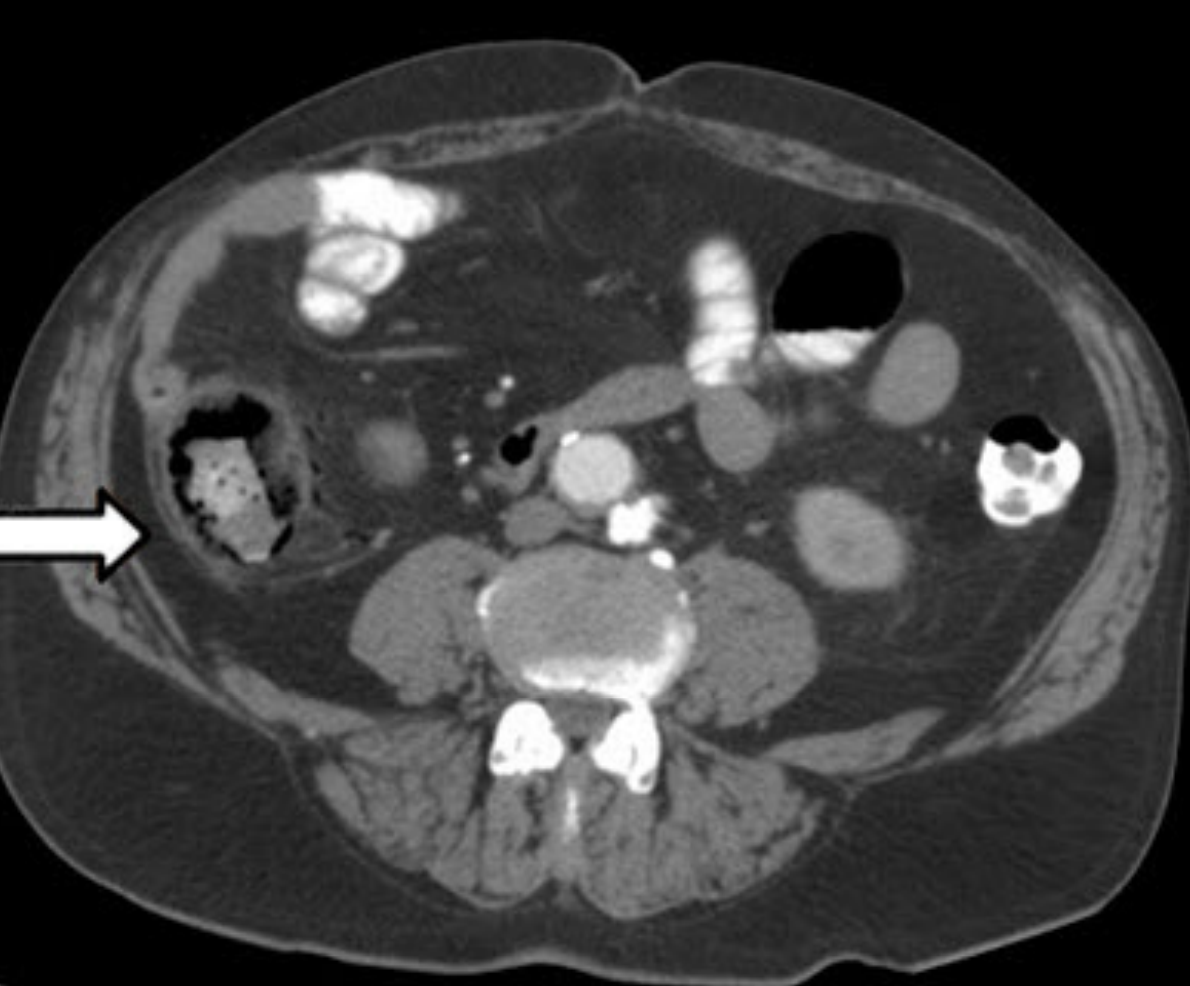

two positives and two negatives?

Positives

* dilated small bowel loops

* thumbprinting

Negatives

* no fecal loading

* no free air

* no rigleers sign